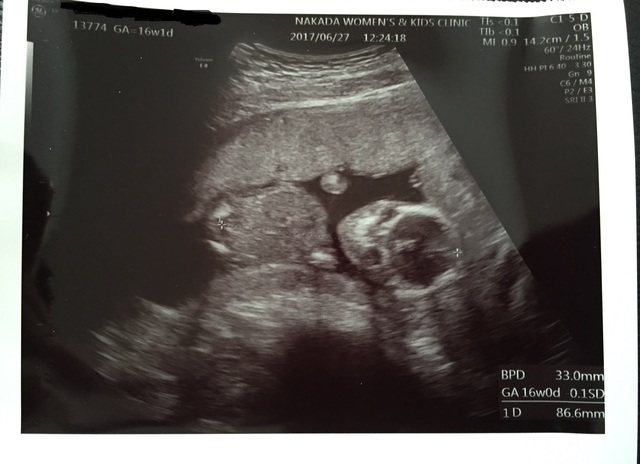

16週1日(16w1d・女の子)|mike0v0 さん(28歳)

エコー写真撮影時のエピソード:

初めて赤ちゃんの全身がはっきり見えたエコー写真です。

自分のお腹の中に人間がいるんだって実感できて妙にそわそわしてしまいました。

それまで体調が良くなかったりしたけどこの子が一生懸命生きてるから私も頑張ろうって思えました。

顔をなかなか見せてくれなかったけど今となってはいい思い出です。